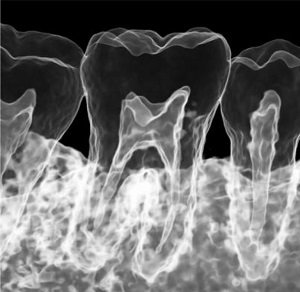

Höchste Detailschärfe

Das Green X ist mit 49μm bei einem FOV von 4x4 cm das Gerät mit einem der weltweit höchsten Auflösungen und der daraus resultierenden Detailschärfe. Dank der byzzEz3D-i Software mit dem Endo-Modul rekonstruiert diese aus ultrahochauflösenden Schichtaufnahmen perfekte 3D Aufnahmen. Diese können dann als Hologramm in allen drei Dimensionen vermessen werden.

Ein ideales Instrument zur Vorbereitung für jede Wurzelkanalaufbereitung und WSR und auch ein hervorragendes Hilfsmittel zur 3D-Visualisierung, Behandlungsplanung und Patientenberatung.

Hierzu stehen heute der modernen Zahnheilkunde vielfältige Technologien zur Verfügung, um die Zähne endodontisch zu diagnostizieren. Neben der 2D-Radiologie und Mikroskopie ist die DVT-Technologie das wichtigste Diagnosewerkzeug.

Die byzzEz3D-i Software mit dem erweiterbaren Endo-Modul rekonstruiert aus den ultra-hochauflösenden Schichtaufnahmen perfekte 3D-Aufnahmen. Die 3D-Endo-Aufnahmen können als Hologramm in allen drei Dimensionen vermessen werden. Sowohl die Bi- und Trifurkation, Kanalanzahl, Kanalverlauf, Kanallänge und -durchmesser sowie die Krümmungsradien können einfach farblich gekennzeichnet werden. Damit ist das 3D-Endo-Modul nicht nur ein ideales Instrument zur Vorbereitung für die Wurzelkanalaufbereitung und WSR, sondern auch ein hervorragendes Hilfsmittel zur 3D-Visualisierung, Behandlungsplanung und Patientenberatung.